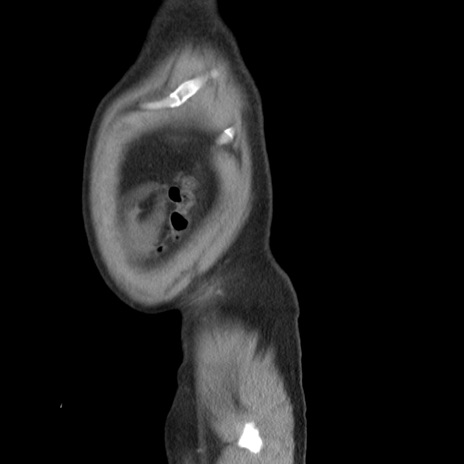

横断像